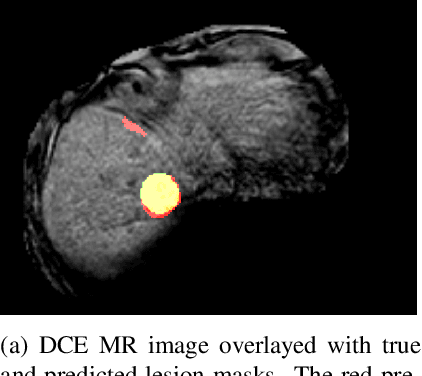

Abstract:Deep learning techniques show success in detecting objects in medical images, but still suffer from false-positive predictions that may hinder accurate diagnosis. The estimated uncertainty of the neural network output has been used to flag incorrect predictions. We study the role played by features computed from neural network uncertainty estimates and shape-based features computed from binary predictions in reducing false positives in liver lesion detection by developing a classification-based post-processing step for different uncertainty estimation methods. We demonstrate an improvement in the lesion detection performance of the neural network (with respect to F1-score) for all uncertainty estimation methods on two datasets, comprising abdominal MR and CT images respectively. We show that features computed from neural network uncertainty estimates tend not to contribute much toward reducing false positives. Our results show that factors like class imbalance (true over false positive ratio) and shape-based features extracted from uncertainty maps play an important role in distinguishing false positive from true positive predictions

Abstract:Despite the successes of deep learning techniques at detecting objects in medical images, false positive detections occur which may hinder an accurate diagnosis. We propose a technique to reduce false positive detections made by a neural network using an SVM classifier trained with features derived from the uncertainty map of the neural network prediction. We demonstrate the effectiveness of this method for the detection of liver lesions on a dataset of abdominal MR images. We find that the use of a dropout rate of 0.5 produces the least number of false positives in the neural network predictions and the trained classifier filters out approximately 90% of these false positives detections in the test-set.